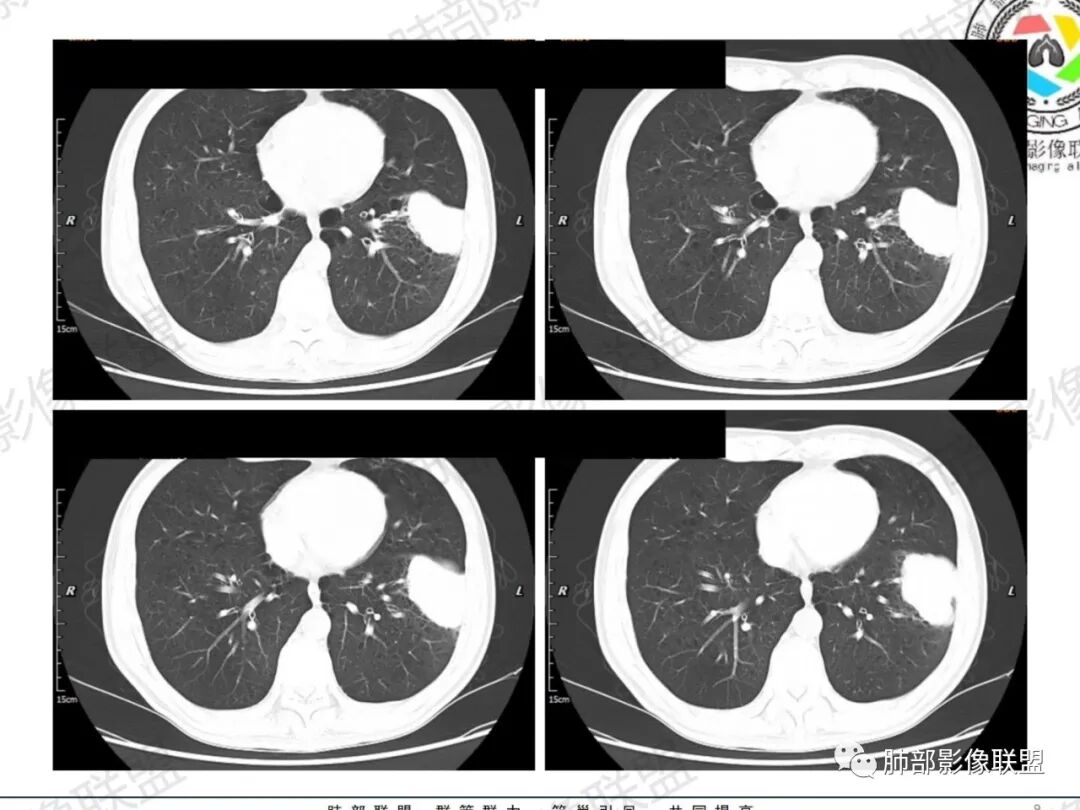

一切∮随缘:左肺下叶不规则肿块,边缘光滑,平直,局部彭隆,分叶,近端支气管堵塞,远端与胸膜相贴,平扫密度尚均匀,增强后不均匀强化,内部可见低密度坏死,胸膜下多发肺气肿,伴双肺散在光滑小结节,实验室肿瘤标志物高,考虑恶性:神经内分泌癌(大细胞),腺癌,鳞癌。

琦遇:恶性没有问题,肺气肿底子、病灶分叶、少许毛刺、叶间胸膜凹陷、部分边缘可见清晰的GGO、胸膜牵拉凹陷、局部胸水、近端支气管截断、部分支气管被推移、占位效应明显、强化特点为不均匀强化、内部有少许沼泽样低强化区,强化部分轻中强化为主、余肺可见转移性结节、左肺上叶似为囊腔型腺癌一枚,肿瘤标志物提示非小、神经内分泌,综合分析考虑大神泌、腺癌、腺鳞癌、鳞癌  同时左肺上叶囊腔型腺癌  肺转移

飞鹰行动:中年人,男性,胸疼入院,左肺下叶占位,张力较高,边界可见分叶,局部可见明显收缩性改变,增强病灶内部有延迟强化表现,考虑恶性病变,大细胞癌伴肺内转移或者囊腔样腺癌伴转移。

蕊:中老年男性,吸烟史,肺气肿背景,左肺上叶类圆形肿块影,边界清晰,边缘凹凸不平,有分叶,支气管进入阻断,临近胸膜栽赃,整体病灶膨隆,局部周围可以清晰ggo,临近叶间裂内凹,轻度强化,并可见多个低密度区,坏死可能,界线不清;肺内多结节,边缘光滑,考虑恶性伴转移,鳞癌、腺癌

傅昌瑜:中老年男性,肺气肿背景,右胸背疼痛1周。CEA、NSE、CYFRA—211升高。左上肺混合磨玻璃结节,内见较多空泡和扩张支气管。左下肺胸膜下肿块,边缘较光滑,深分叶,似有血管进入,与支气管关系不清,内见不均匀强化,见沼泽地样坏死,有胸膜栽赃。另两肺多发圆形小结节。考虑恶性并肺内转移,多原发可能性大,左上肺腺癌,左下肺病理难以判断,小细胞癌?鳞癌?

小锁:中老年男性,肺气肿背景,右胸背疼痛1周。CEA、NSE、CYFRA—211升高。左上肺混合磨玻璃结节,边界清楚,内见较多空泡。左下肺肿块,边缘清楚,深分叶,有血管和支气管进入,胸膜凹陷。另两肺多发圆形小结节。考虑双发原位癌,左上肺腺癌,左下肺大神泌或腺鳞癌可能,肺内转移。

蓝天白云:中年男性,肺气肿背景,左肺下叶肿块,边缘膨隆,有分叶,内有湖泊样坏死,有轻中度强化,局部胸膜栽赃,收缩力不强,周围见肺气肿征象。左肺上叶混合磨玻璃影,边界清楚,考虑都是恶性,左上肺iac,左下肺腺鳞癌,或大细胞肺癌可能。两肺多发结节,考虑转移

毛勤香:老年男性,肺气肿背景,左肺下叶肿块,分叶,边缘光滑,土豆块样,细支气管闭塞,增强轻度不均匀强化,似有坏死,左肺另见多发结节,淋巴结未见明显肿大,恶性确定,吸烟史,鳞癌破坏力强,侵袭力差,多原发的一般很少多于3个,故排后,首先考虑神经内分泌癌,局部血管穿行,鉴别淋巴瘤

周太狼:中年男性,吸烟、高血压史,肿瘤指标升高,肺气肿背景下,左肺下叶肿块影,分叶、膨隆、未跨叶裂,支气管截断,不均匀强化。另双肺多发结节及磨玻璃影,左肺上叶混合磨玻璃,内可见多发空泡影。整体考虑恶性,肺癌伴肺内转移,左下肺鳞癌?神经内分泌癌?左肺上叶囊腔腺癌?